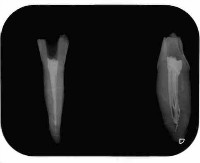

根管の中に入れた最終的なお薬が根の先までしっかり入って、歯の間のコントラストがはっきりしてます。

根管の細菌に感染した歯質をしっかりとって、最終的なお薬で隙間なく埋める事で細菌が感染増殖するのを防ぎます

しっかりと感染歯質をとり、緊密に最終的なお薬をつめているので歯とお薬のコントラストもはっきりしています。